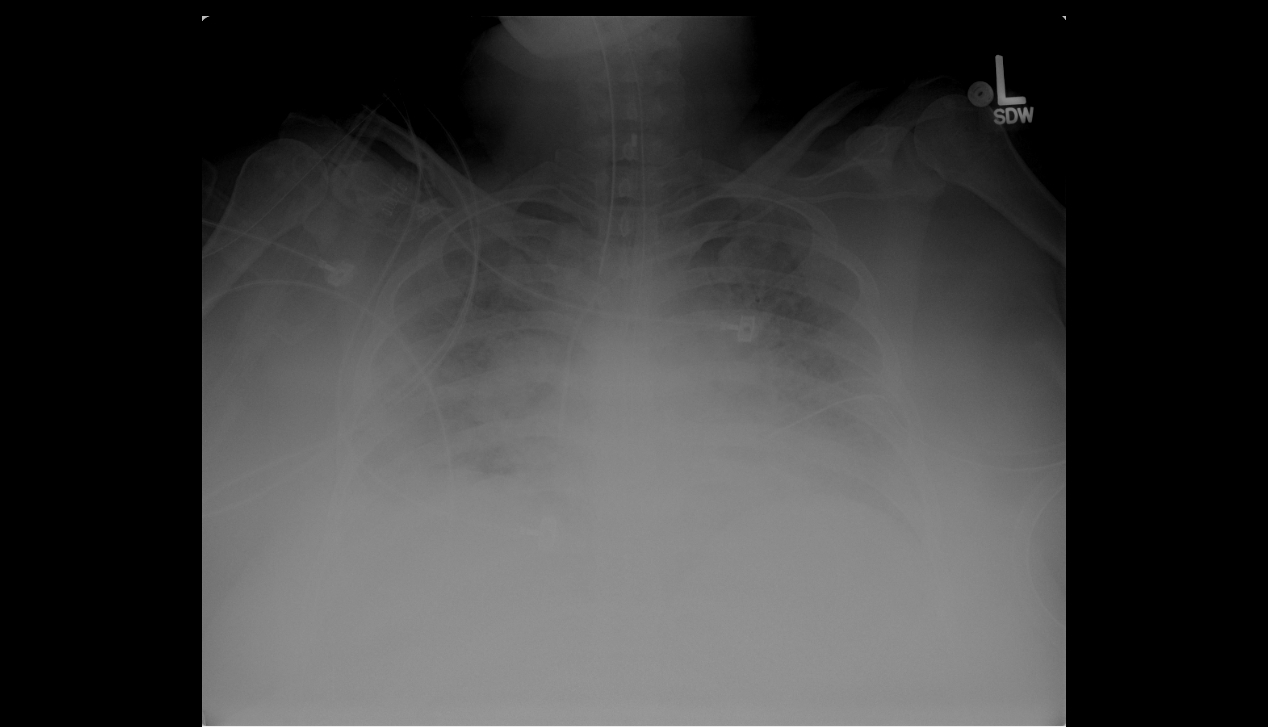

Chest radiograph is shown in Figure 1.

Figure 1. Portable chest radiograph